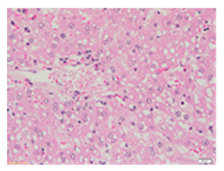

Liver wet weights of all rat groups showed no significant differences (Table 8). According to histochemical hematoxylin and eosin (H&E) staining, treatment with the highest dose of MPE (1000 mg/kg BW) did not result in morphological changes in the liver tissue (B) when compared with DI water treatment (A). Obviously, CCl4 induction (ip)/DI water treatment (po) caused hepatoxicity, which was indicated by a severe degree of fatty changes and fatty cysts in the liver tissue (C), whereas pretreatments of silymarin (100 mg/kg BW, po) effectively decreased the degree of fatty changes and fatty cysts in the liver when compared with the CCl4/DI water group. Indeed, MPE (250 and 1000 mg/kg BW, po) lowered the degree of lipid accumulation in the liver; inversely, MPE (500 mg/kg BW, po) exhibited a severe degree of lipid accumulation. Apparently, taking paracetamol (2 g/kg BW) induced a severe degree of hepatic necrosis when compared with rats that had not received the treatment. Similarly, pretreatments of silymarin (100 mg/kg BW, po) and MPE (250 and 1000 mg/kg BW, po) revealed a mild degree of hepatic necrosis, while MPE (500 mg/kg BW, po) revealed a moderate to severe degree of hepatic necrosis. Accordingly, the findings imply that the consumption of MPE (1000 mg/kg BW) was not harmful to the liver of healthy rats, while MPE (250 mg/kg BW) did improve fat deposition in the livers of CCl4-fed rats and offered protection against liver cell damage in paracetamol-fed rats.

Wet weight values (mean ± SD) and H&E staining of liver from rats with hepatotoxicity induced by CCl4 and paracetamol.